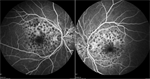

A 39-year-old healthy female veteran initially presented with visual distortion in both eyes for a few months. She denied a history of trauma, pain, floaters, chemical or laser exposure, or photopsias. The patient reported no family history of ocular disease. Best-corrected visual acuity (BCVA) was 20/20 in both eyes. Pupils, motility, visual fields by confrontation, and intraocular pressure were normal. Slit lamp examination was unremarkable. Dilated funduscopic examination revealed multiple areas of hypopigmentation with interspersed RPE clumping in the central macula bilaterally (Figure 1). The peripheral retina demonstrated no abnormalities. Fluorescein angiography revealed multiple hypofluorescent lesions in the macula with encircling hyperfluorescence (Figure 2).

The patient was lost to follow-up and presented 11 years later when she was 50-years-old complaining of continued decline in vision. BCVA was 20/20 in both eyes with a minor myopic refractive error. Dilated fundus examination now showed a flat central area of hypopigmentation with irregular borders, which appeared larger than that in previous exams (Figure 3). A greater degree of RPE pigment clumping was seen within the lesion. The nerve, vessels, vitreous, and peripheral retina were within normal limits. OCT showed bilateral parafoveal irregularity at the level of the RPE (Figure 4). FA showed a larger confluent area of central hyperfluorescence with scattered hypofluorescence (Figure 5).